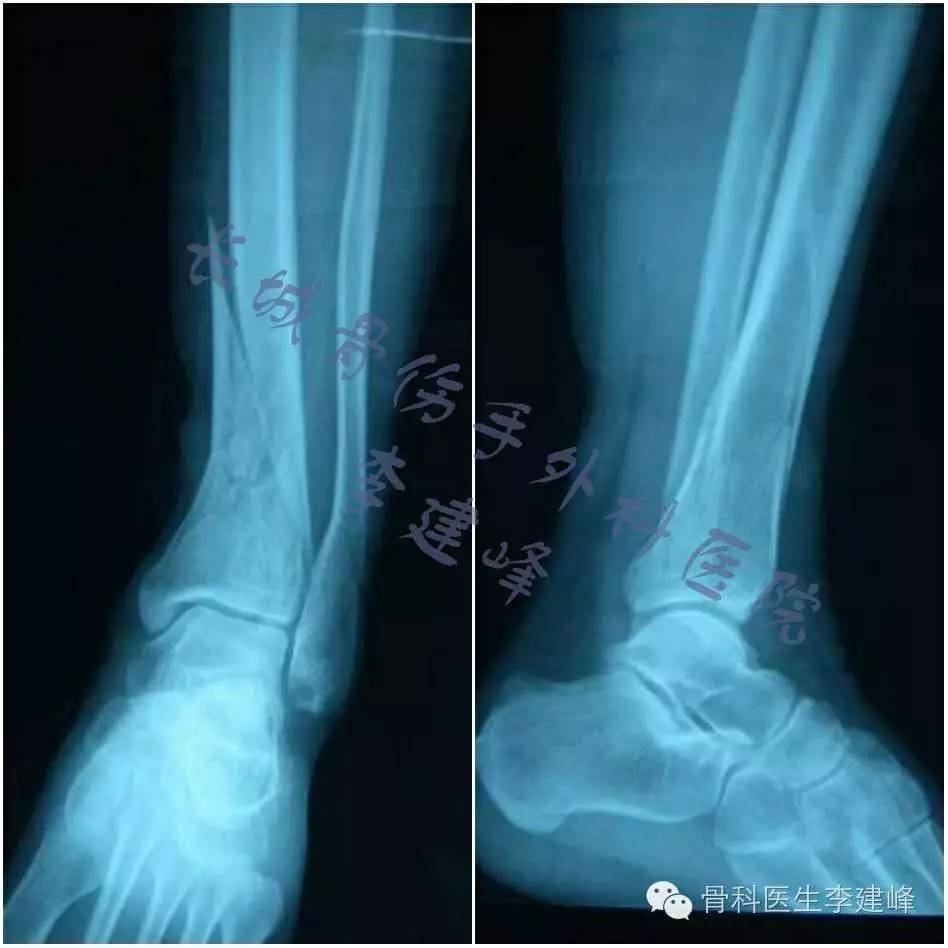

双侧跟骨骨折 左腓骨骨折 医联

左腿腓骨骨折韧带撕裂 手术恢复mark 知乎

踝关节骨折病例 请问腓骨是否需要复位固定 骨科专业讨论版 丁香园论坛